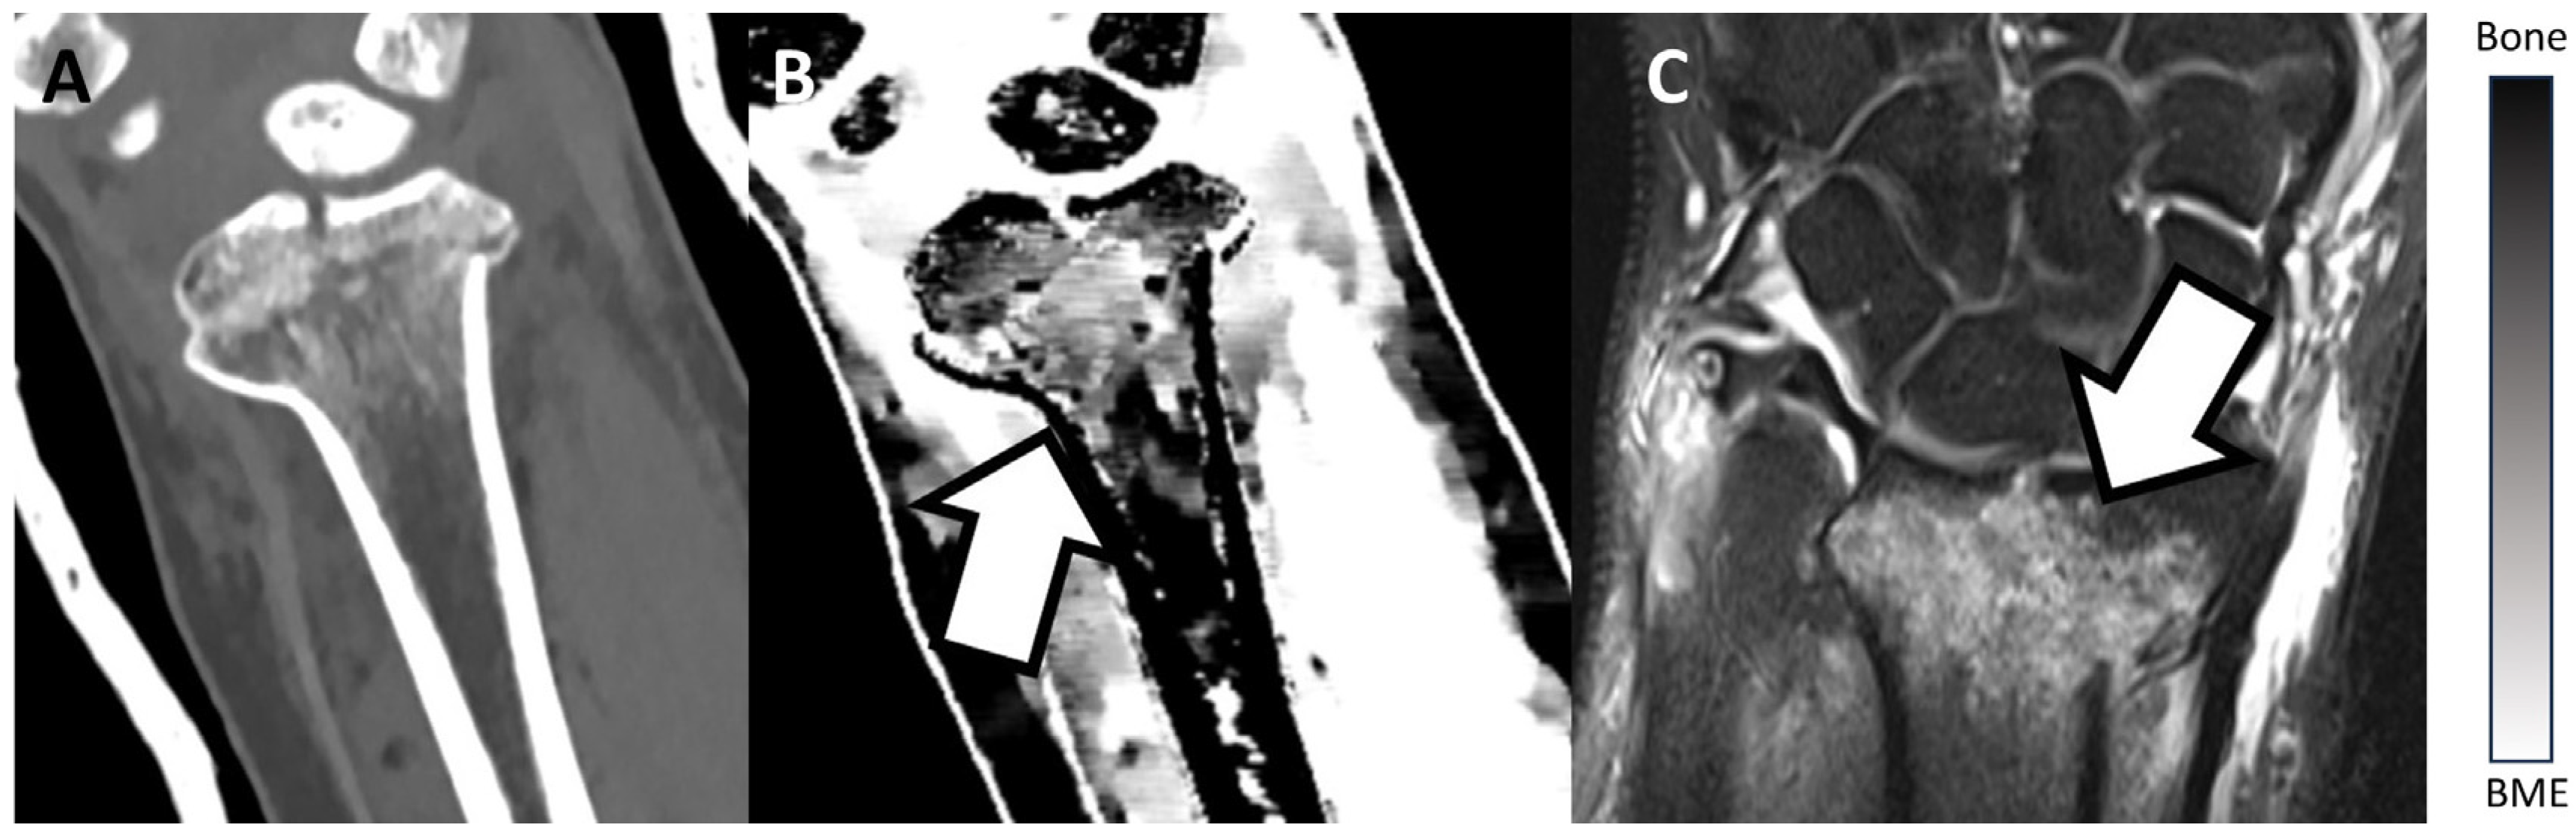

Figure 2 and Figure 3 show examples of BME on TMD images in different locations. Figure 2 presents an example of a fractured proximal tibia on conventional CT images and the TMD tool, whereas Figure 3 shows a fractured distal radius.

Figure 2.

Fractured proximal tibia of a patient on a conventional CT image (A), on the TMD tool (B), and the corresponding MRI (C). The BME (white arrow) is visible on the TMD tool and the corresponding MRI, but it is not detectable on the conventional CT image. Additionally, a bar chart shows the density/intensity levels between normal bone and BME.